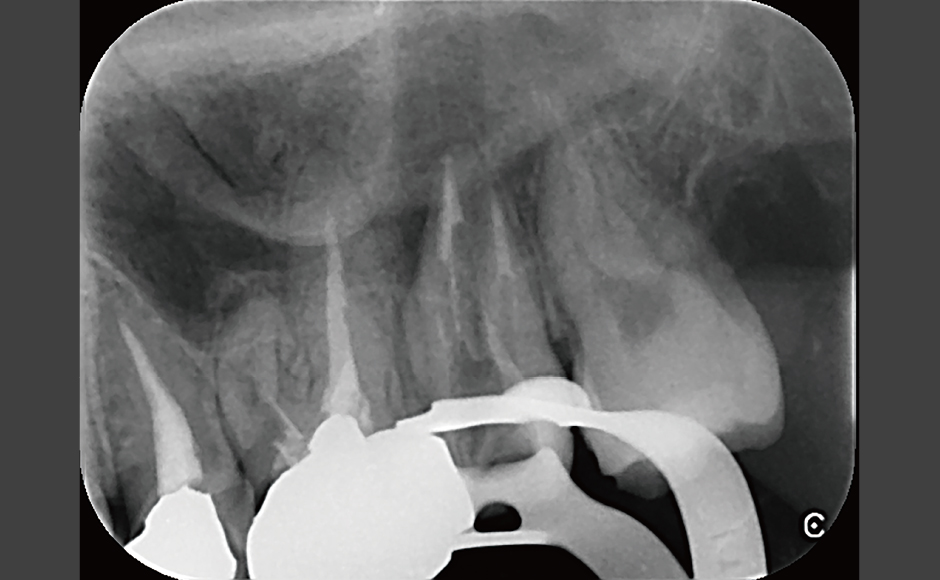

歯内療法の症例紹介 歯の保存を可能にする歯内療法の力

症例.1:穿孔を伴う根尖性歯周炎に対して非外科的歯内療法を行った症例

症例.2:外科的歯内療法を併用して根尖性歯周炎の治療を行った症例